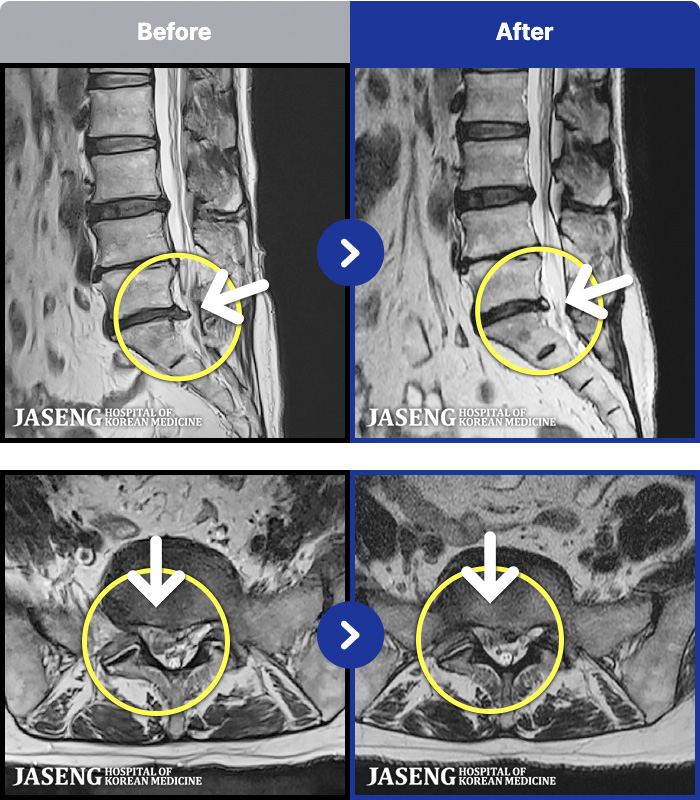

62 MRI ũ ʸ Ȯϼ.

ȯںп Ǹ ǿ ԿǾ, ο ġ ۿ Ƿ ġḦ Ͻñ ٶϴ.